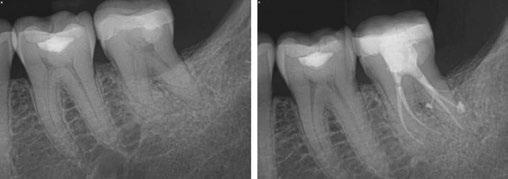

1: Radiograph of tooth No. 18. The image on the right illustrates how the GentleWave Procedure cleans and clears all portals of exit

Let’s examine a case of a 58-year-old male who presented to my office in pain. He was referred as an emergency for consultation and treatment on either tooth No. 18 or 19. The patient presented with pain that had been on and off for over a month. The patient’s chief complaint was pain to cold and hot that lingered and now was spontaneous. On examination, tooth No. 19 responded to pulp testing within normal limits and was negative to percussion. Tooth No. 18 had a lingering sensitivity to cold, and a diagnosis of irreversible pulpitis and symptomatic apical periodontitis was made.

As you can see from final radiographs, the GentleWave Procedure’s ability to clean out and clear all portals of exit is on clear display here. I would not have had a similar outcome if I did not use the GentleWave Procedure.